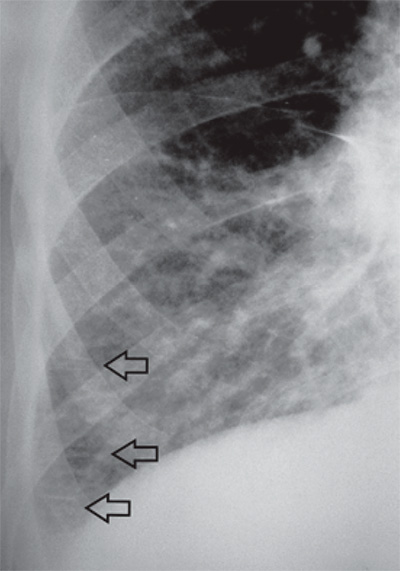

Рисунок 2. Линии Керли типа В: фрагмент рентгенограммы правого легочного поля в прямой проекции. Линии Керли типа В (см стрелки) определяются в типичном месте – над реберно-диафрагмальным синусом